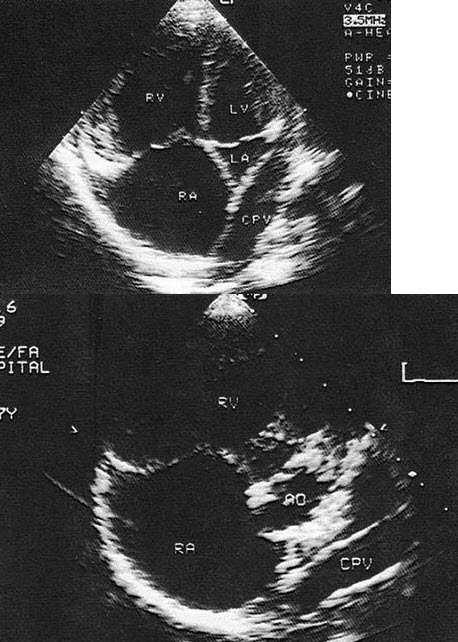

30、单项选择题

根据心尖四腔切面声像图所示,超声诊断为()